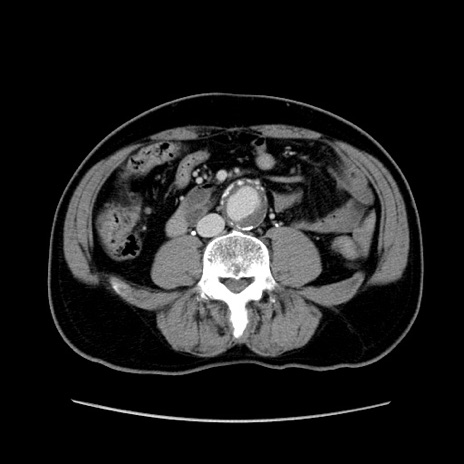

症例34(横断像)

【症例】60歳代 男性

【主訴】右鼠径部膨隆

【現病歴】1年程前より右鼠径部膨隆あり。自己にて還納可能だったため放置していた。3時間前より右鼠径部の脱出を認め、還納困難となり受診。

【身体所見】右鼠径部に小児頭大の膨隆あり。弾性硬であり、用手還納は困難。左鼠径部にも膨隆を認める。脱出はなし。